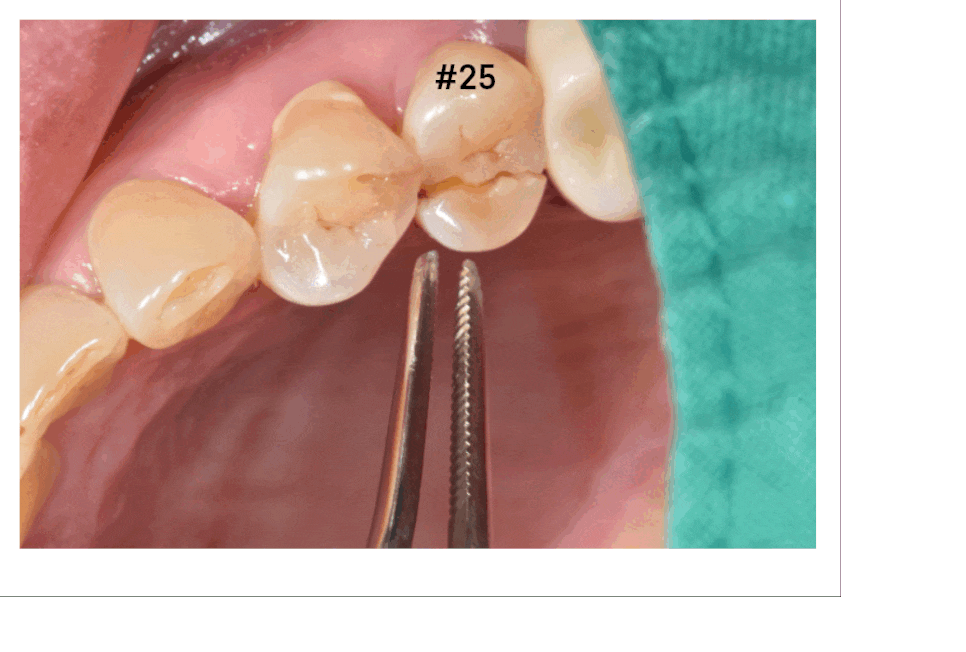

입안 검사를 해보았습니다.

치아가 반으로 쪼개졌네요.

이런 경우가

치아가 쪽이 나간 경우입니다.

주로 딱딱한 음식을 잘못 씹었을 때

치아 쪼개짐이 발생하는데요.

이건 치아가 반으로 분리된 거라

발치 후 임플란트 계획을 잡았습니다.

치아 쪼개짐 옆에 잇몸에서도 농이 나오네요

농 = 고름

치아 잇몸 뼈를 계속 녹이는 상황이라

문제가 되는 치아 2개를 발치 후 임플란트 하기로 하였습니다.